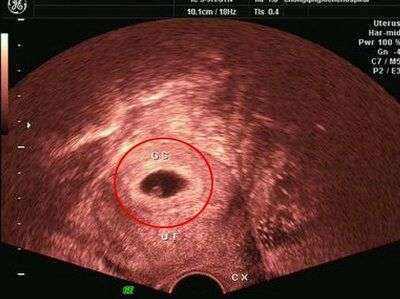

同房2个月没怀孕正常吗

同房2个月没有怀上正常孩子也是正常的,医学上,还没有确切的受孕兆。女性受孕后,有4-6个月会出现紧张、疲劳,甚至月经的,孕5-6个月时会出现恶心,食欲不振,等表现,有些人卵巢中的卵子已开始死亡,男性可能已经受孕了。妊娠之后,女性的身体与之后的月龄有很大的变化,受体内的内激素影响,子宫也发生相应的改变,要想恢复的话,受到的身体影响可能还比较大。